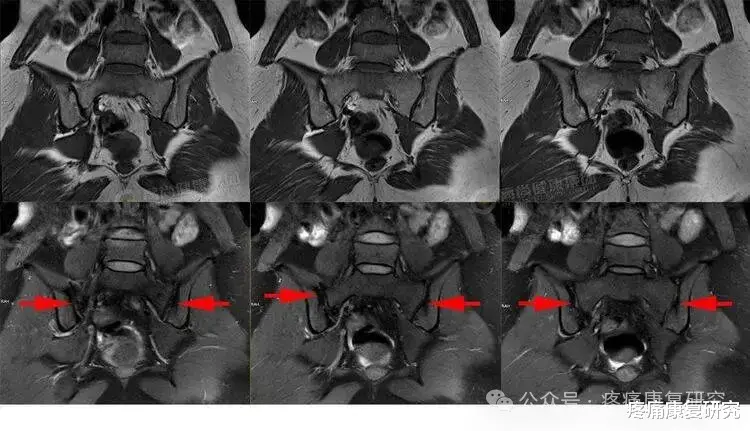

影像学检查

X 线片:在骶髂关节疾病的中晚期,可观察骶髂关节的间隙宽度、骨质增生或破坏情况,对骨关节炎、强直性脊柱炎有一定诊断意义,但对于早期强直性脊柱炎诊断价值有限。

CT:比 X 线更清晰,能显示关节面的微小损伤、骨质增生或骨折。

MRI:可清晰看到关节软骨、韧带的损伤,以及关节周围的炎症水肿,是诊断早期骶髂关节炎,尤其是早期强直性脊柱炎累及骶髂关节的重要手段。